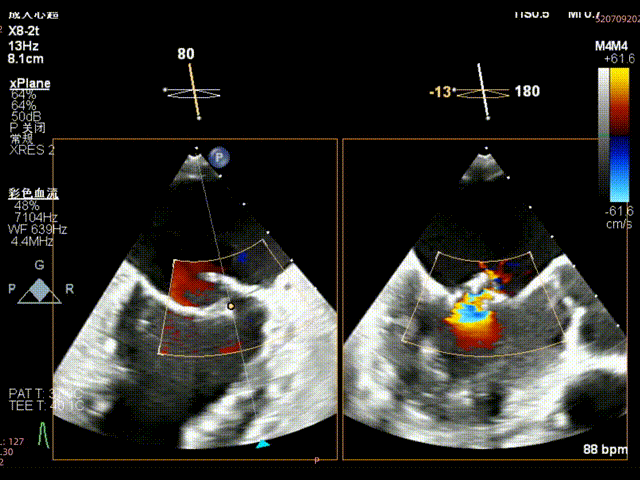

术前食道超声示: 二尖瓣2区前叶大范围脱垂伴后叶栓系。

术前食道超声-2D血流

术前食道超声-3D血流